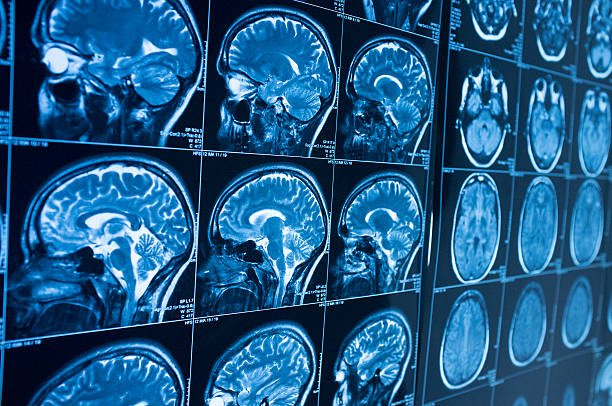

Over time, similar reports surfaced from multiple countries, expanding the geographic scope of concern and prompting coordinated investigations. Governments faced immediate challenges in interpreting the reports. Some medical evaluations identified signs consistent with mild traumatic brain injury, even though no conventional physical trauma had occurred. Neuroimaging and clinical testing revealed abnormalities in certain patients, while other examinations produced inconclusive or inconsistent findings.

The outcome, however, was not what investigators anticipated. After testing the device, the scientist developed significant neurological symptoms. Medical evaluations later indicated that the researcher had suffered brain damage, though the precise mechanism responsible for the injury has not been publicly detailed. The severity of the condition triggered immediate concern among authorities, leading to consultations with international experts and the involvement of multiple government agencies seeking to understand both the technical and medical dimensions of the incident.

Investigators reportedly concluded that the scientist’s symptoms did not align perfectly with previously documented cases associated with Havana Syndrome. This distinction has complicated efforts to interpret the findings. On one hand, the occurrence of neurological injury following exposure to experimental microwave emissions has drawn attention to potential biological risks associated with high-intensity energy pulses. On the other hand, the differences between the researcher’s condition and earlier reports suggest that the relationship between directed energy and observed symptoms may be more complex than originally assumed.

Beyond the immediate medical consequences, the experiment has taken on broader symbolic significance. A project intended to challenge or disprove the plausibility of energy-based explanations instead produced an injury consistent with serious neurological harm. Although this does not confirm that such devices are responsible for reported anomalous health incidents, it demonstrates that powerful microwave emissions can produce measurable biological effects under certain conditions. The finding has intensified scientific interest in the potential interaction between electromagnetic energy and human neural function.